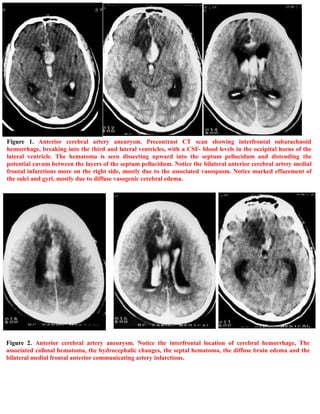

A 40-year-old male patient was found unconscious on a toilet with a ruptured anterior communicating artery aneurysm and subarachnoid hemorrhage. CT scans showed interfrontal subarachnoid hemorrhage breaking into the ventricles with blood in the occipital horns and bilateral anterior cerebral artery infarctions, more severe on the right side. The document describes images of the ruptured anterior communicating artery aneurysm and associated hemorrhaging and edema. It also provides information on accessing updated case publications on the author's website.